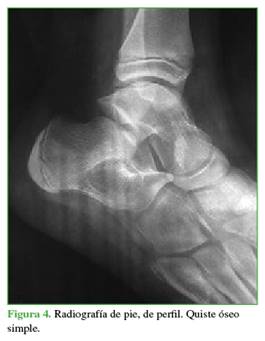

Se planteó el diagnóstico diferencial de tumor benigno polilobulado de calcáneo entre quiste sinovial simple óseo (Figura 4), QOA (Figura 5) o lipoma intraóseo (Figura 6).